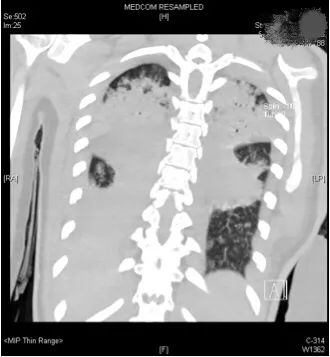

评估结果不容乐观,呼吸机的支持水平要求很高,100%纯氧条件下小文体内的氧分压才勉强达标,持续高烧超过40摄氏度,CT复查提示两肺几乎全部实变,炎症指标非常高。

小文的影像检查显示,双肺几乎完全实变